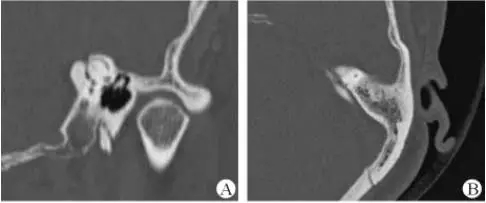

1、上半規(guī)管裂綜合征

內(nèi)耳結(jié)構(gòu)非常微妙。即使是內(nèi)耳中大頭針樣的孔洞也能造成平衡失調(diào)。患者常常不敢進(jìn)行如走路或轉(zhuǎn)頭的日常活動(dòng)。此罕見(jiàn)疾病,醫(yī)學(xué)專家預(yù)估至少影響著人口的1%。可造成惡心,眩暈以及對(duì)噪聲極高的敏感性。病人還常常抱怨他們能聽(tīng)到血管跳動(dòng)的聲音。其中一位患者曾告訴耳科專家,他都能聽(tīng)到自己轉(zhuǎn)動(dòng)眼睛的聲音。

醫(yī)生若懷疑此病將會(huì)安排內(nèi)耳CT掃描。在大多數(shù)案例中,一旦此病被耳鼻喉科醫(yī)生或其它聽(tīng)力健康專家確診,則可實(shí)行手術(shù)治療。外科手術(shù)風(fēng)險(xiǎn)包含聽(tīng)力損失以及神經(jīng)損傷;重建及復(fù)原需內(nèi)耳的治療以及大腦的重塑。